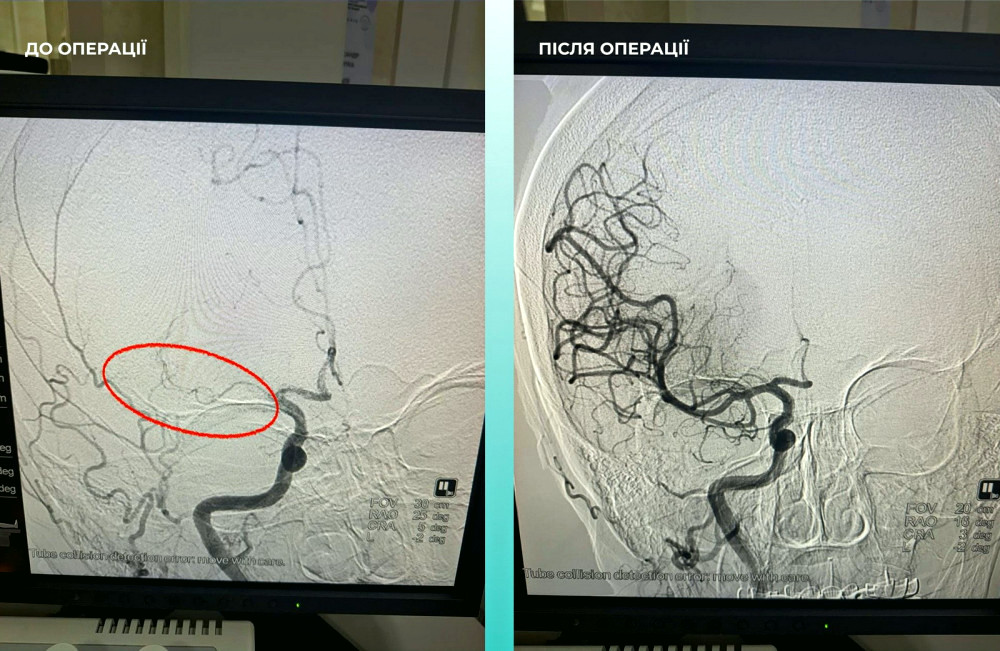

Команда фахівців ухвалила рішення про проведення одночасної тромбектомії обох артерій, що стало критично важливим кроком.

Операція завершилась успіхом: пацієнтка почувається набагато краще, вона вже в свідомості та може рухати кінцівками.